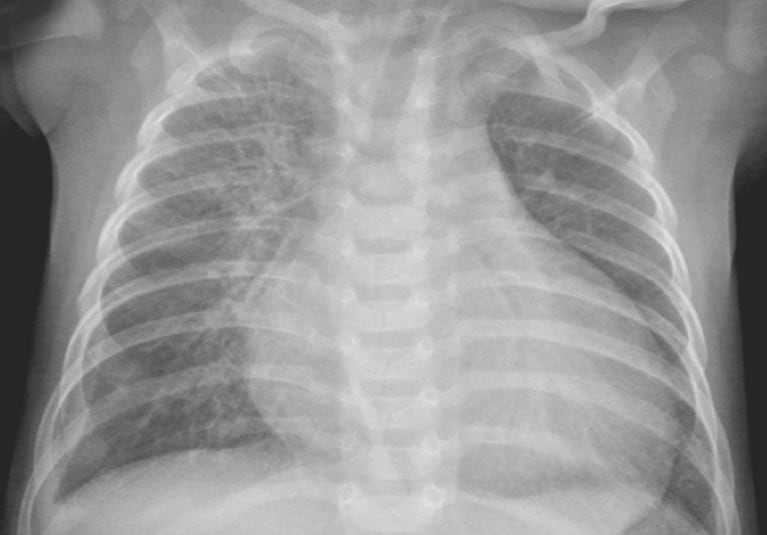

A normal chest X-ray typically shows:

- Clear, symmetrical lung fields without masses or fluid

- A heart size within normal limits

- No visible fractures or abnormalities in the bones

- Normal size and shape of the diaphragm

- No enlarged lymph nodes or abnormal masses

It’s important to note that “normal” can vary slightly from person to person, and radiologists take into account factors such as age, sex, and medical history when interpreting results.

Normal: | The lungs look normal in size and shape, and the lung tissue looks normal. No growths or other masses can be seen within the lungs. The pleural spaces (the spaces surrounding the lungs) also look normal. |

The heart looks normal in size, shape, and the heart tissue looks normal. | |

The bones including the spine and ribs look normal. | |

The diaphragm looks normal in shape and location. | |

No abnormal collection of fluid or air is seen, and no foreign objects are seen. | |